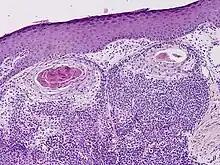

Hidradenocarcinoma

Hidradenocarcinoma (also known as malignant hidradenoma, malignant acrospiroma, clear cell eccrine carcinoma, or primary mucoepidermoid cutaneous carcinoma) is a malignant adnexal tumor of the sweat gland. It is the malignant variant of the benign hidradenoma. It may develop de novo or in association with an existent hidradenoma.[1]

Clear cell hidradenocarcinoma